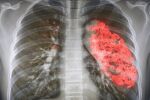

6. Пневмония

Пневмонията е остро инфекциозно възпаление на белите дробове, което може да се наблюдава при пациенти от различна възраст. Вирусните инфекции през есента и зимата обикновено са най-честата причина за развитие на пневмония. Заболяването се развива при инфекция с парагрип, грип А, В, С, аденовируси, коронавируси и други, когато няма лечение.

Бактериалната пневмония се лекува с антибиотици, като правилното предписване на антибиотици е от решаващо значение за избягване на антибиотична резистентност и други възможни усложнения. Обикновено правилно подбраните антибиотици, почивка, нестероидни противовъзпалителни средства и много течности са достатъчни за пълно възстановяване.

Лечението на вирусната пневмония има за цел да елиминира водещите симптоми и усложнения, като пациентите трябва да спазват диета и режим на почивка, да приемат лекарства и при необходимост да получават други терапии.